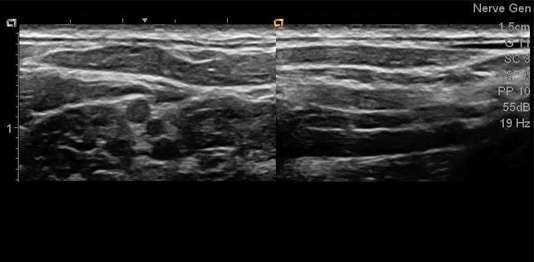

- Utilice tecnología de visualización de agujas mejorada con guía dentro y fuera del plano, lo que puede ayudar a reducir punciones imprecisas y mejorar la guía del procedimiento.

- Vea claramente todo el campo de visión con imágenes de alta calidad y alta resolución utilizando la exclusiva arquitectura de procesamiento de imágenes Pixelformer del sistema.